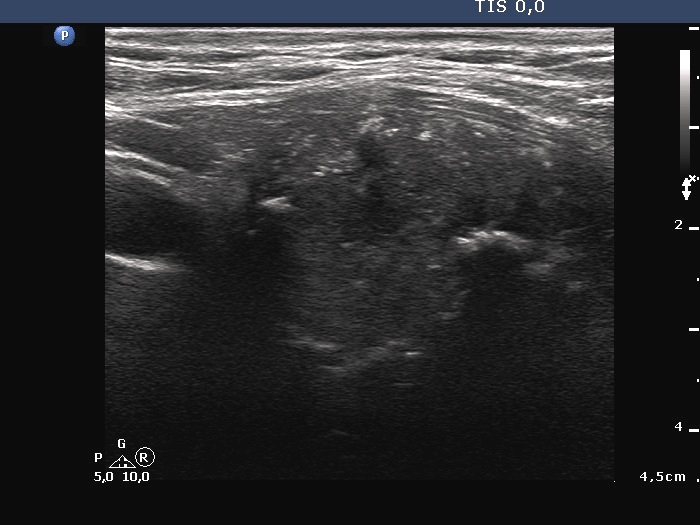

Ultrasonography. The thyroid was echonormal. A large hypoechoic nodule occupied almost the entire right lobe. The nodule showed various intranodular echogenic figures, including microcalcifications, macrocalcification and non-specific figures. The borders were indistinctive. The lesion was suspicious spreading extrathyroidal.